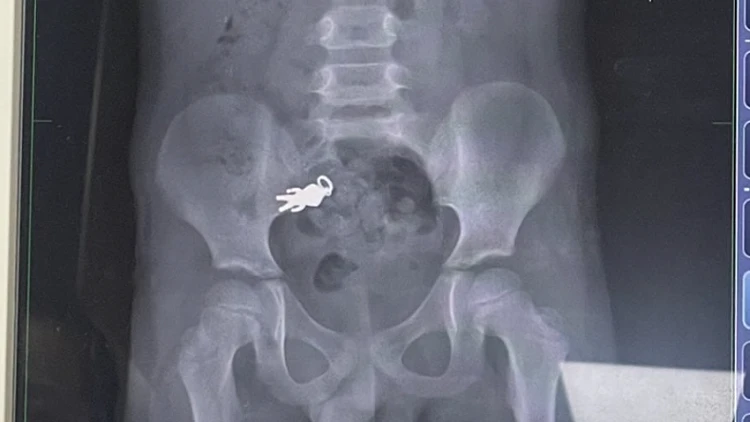

הרופאים בבית החולים לואודונג בו-אי ערכו צילום רנטגן וגילו כי החפץ נתקע במעיים. ד"ר שיאה צ'ינטונג, שטיפל בילד, סבר כי מאחר ולא הופיעו סימנים של כאבים חריפים או חסימה, לא היה צורך בניתוח. הוא המליץ למשפחה להמשיך במעקב בבית, והזהיר כי הופעת כאבים חזקים, הקאות או עצירות ממושכת תחייב טיפול מיידי.

הצילום בו נראה מחזיק המפתחות בבירור, פורסם על ידי בני המשפחה ברשתות החברתיות ועורר תגובות רבות. גולשים רבים הגיבו בהומו על "מסע הגיבור" בתוך גופו של הילד. אחרים הביעו ביקורת כלפי ההורים על שלא השגיחו על ילדם.